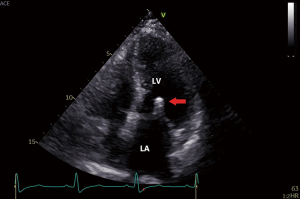

Twelve-lead electrocardiogram showed ST-T segment depression and signs of left ventricular hypertrophy. Transthoracic echocardiography (TTE) showed asymmetric septal hypertrophy with a maximal wall thickness of 16 mm at the LVOT level. Transesophageal echocardiography (TEE) revealed significant SAM of the anterior mitral leaflet (Figure 1, Video 1), causing dynamic LVOT obstruction (Figures 2,3) and severe MR (Figure 2, Video 2). On Valsalva maneuver, the LVOT pressure gradient reached 233 mmHg. Her left atrium was dilated and pulmonary artery systolic pressure was elevated. Reversed systolic wave was observed in the pulmonary vein flow (Figure 4). No abnormal muscle bundles were observed on imaging, including TEE and TTE.